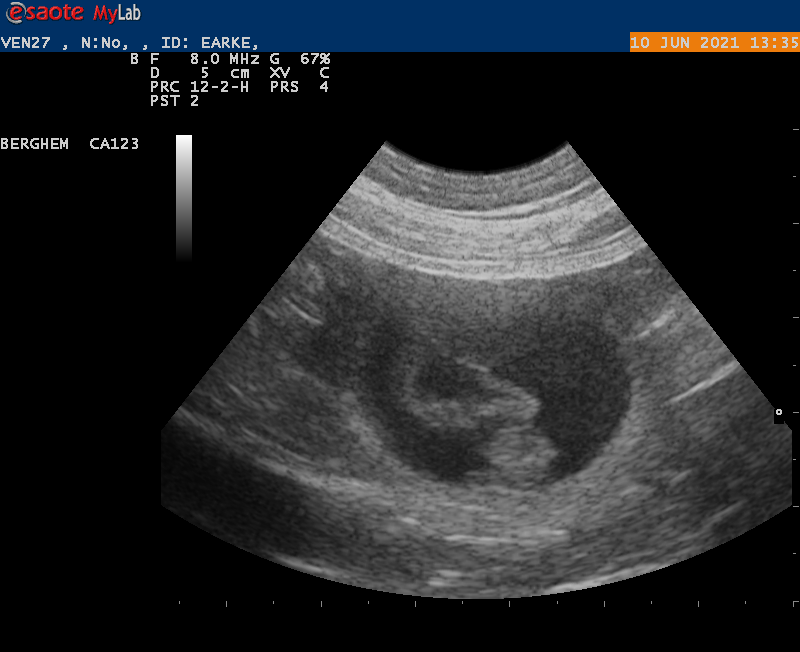

10-6-2021

Vanmiddag zijn we naar de dierenarts geweest met Earke voor een echo. Super goed nieuws: Earke is drachtig. We hebben zelfs al de hartjes zien kloppen van de pups.

Als alles goed blijft gaan krijgen we rond 14 juli een nestje van Earke en Douwe.